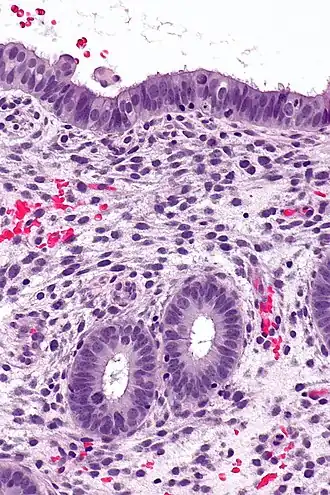

Structure

The endometrium consists of a single layer of columnar epithelium plus the stroma on which it rests. The stroma is a layer of connective tissue that varies in thickness according to hormonal influences. In the uterus, simple tubular glands reach from the endometrial surface through to the base of the stroma, which also carries a rich blood supply provided by the spiral arteries. In women of reproductive age, two layers of endometrium can be distinguished. These two layers occur only in the endometrium lining the cavity of the uterus, and not in the lining of the fallopian tubes where a potentially life-threatening ectopic pregnancy may occur nearby.[4][5]

- The functional layer is adjacent to the uterine cavity. This layer is built up after the end of menstruation during the first part of the previous menstrual cycle. Proliferation is induced by estrogen (follicular phase of menstrual cycle), and later changes in this layer are engendered by progesterone from the corpus luteum (luteal phase). It is adapted to provide an optimum environment for the implantation and growth of the embryo. This layer is completely shed during menstruation.

- The basal layer, adjacent to the myometrium and below the functional layer, is not shed at any time during the menstrual cycle. It contains stem cells that regenerate the functional layer,[1] which develops on top of it.

Cycle

The functional layer of the endometrial lining undergoes cyclic regeneration from stem cells in the basal layer.[1] Humans, apes, and some other species display the menstrual cycle, whereas most other mammals are subject to an estrous cycle.[2] In both cases, the endometrium initially proliferates under the influence of estrogen. However, once ovulation occurs, the ovary (specifically the corpus luteum) will produce much larger amounts of progesterone. This changes the proliferative pattern of the endometrium to a secretory lining. Eventually, the secretory lining provides a hospitable environment for one or more blastocysts.